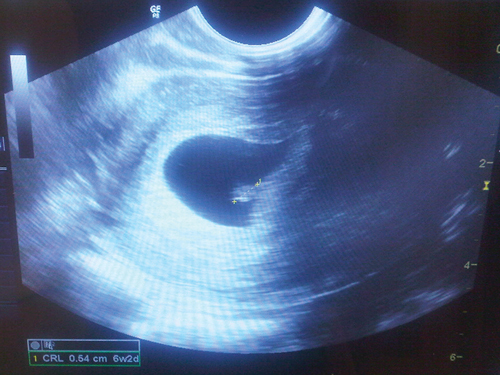

Fifteen days after oocyte retrieval, the woman had a β-hCG level of 259 IU/L and a progesterone level of 71.6 nmol/L. She continued vaginal progesterone treatment. At 5 weeks, she had a β-hCG level of 5140 IU/L and a progesterone level of 76.4 nmol/L. A vaginal ultrasound was performed at 6 weeks and 3 days, in November 2012, and a viable intrauterine pregnancy was confirmed, with a fetal heart rate of 120 beats/min (Box).